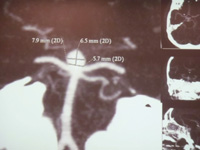

AngioTAc de aneurisma paraclinoideo esqº.